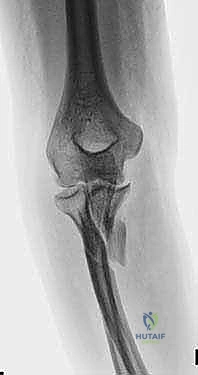

FIG 1 • Plain AP radiograph typically demonstrates fracture pattern.

FIG 1 • Plain lateral radiograph typically demonstrates fracture pattern.

FIG 1 • Plain oblique radiograph typically demonstrates fracture pattern.